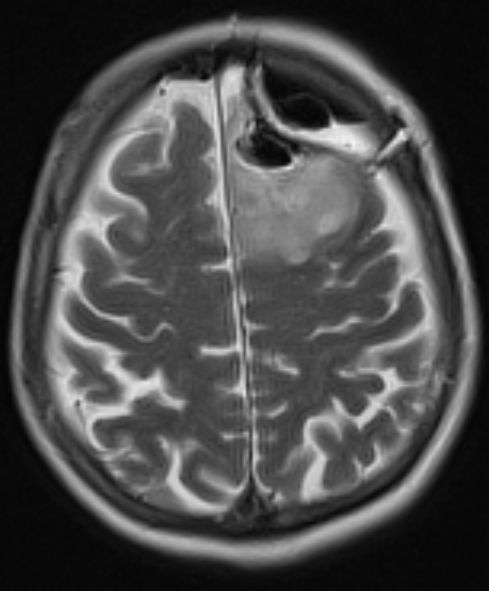

post OP |

MRT T2 Blade![]() |

Nach Teilresektion erfolgte die Bestrahlung mit 50,4Gy, ED 1,8Gy. | ||